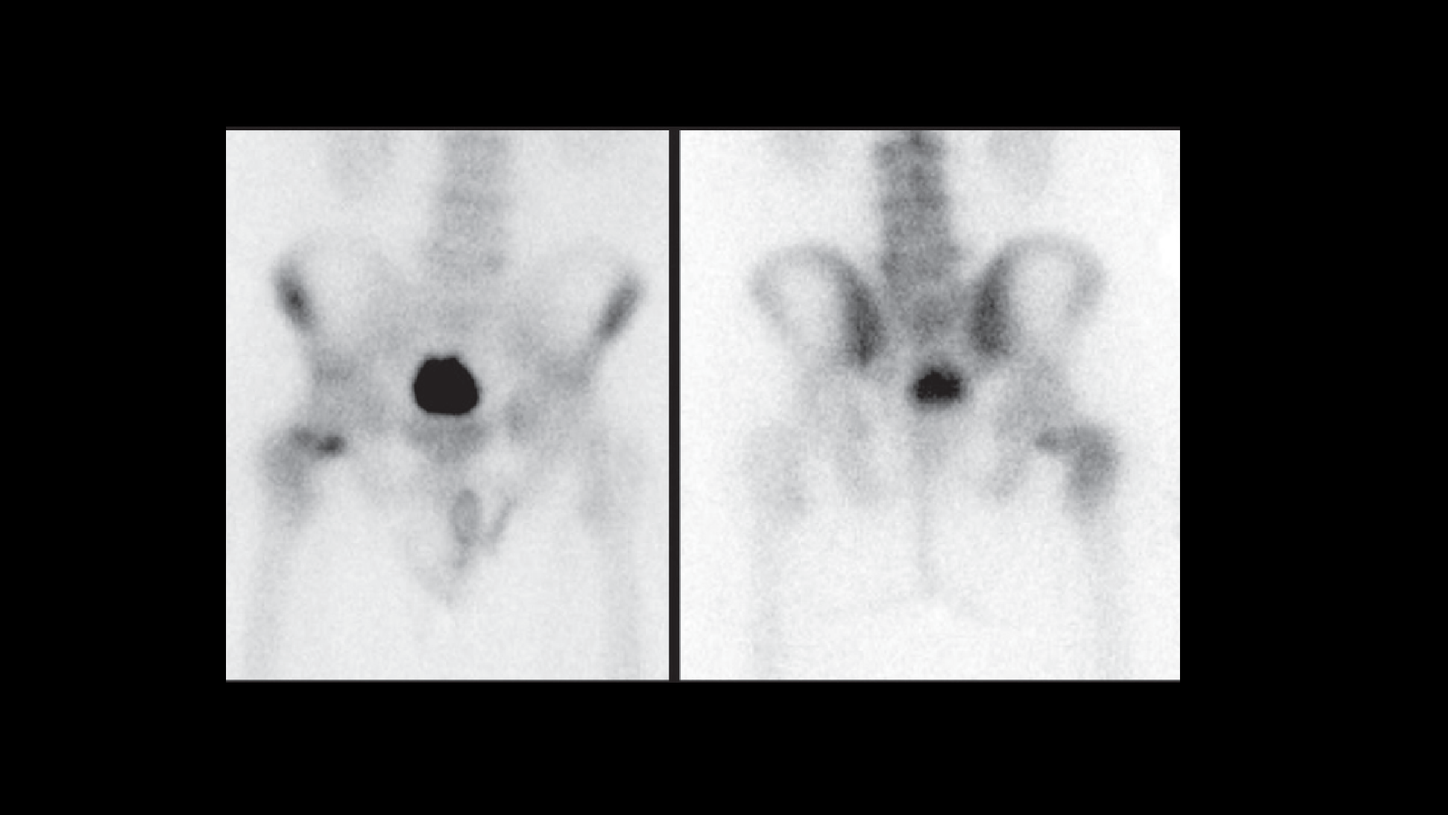

An xSPECTTM study was performed three hours following IV injection of 27.4 mCi 99mTc MDP. Initial planar images were followed by xSPECT acquisition. 3D iterative reconstruction and xSPECT BoneTM reconstructions were performed for comparison.

xSPECT Bone sharply defines the focal area of increased uptake in the medial margin of the neck of the femur adjacent to the femoral head. The rest of the femoral neck and the intertrochanteric crest also show slightly increased uptake. The femoral head uptake appears normal. Compared to SPECT (AC), the xSPECT Bone images show sharper margins of the hypermetabolic foci in the femoral neck as well as sharper delineation of the femoral head, trochanteric regions, intertrochanteric crest, and the rest of the pelvis and acetabulum.